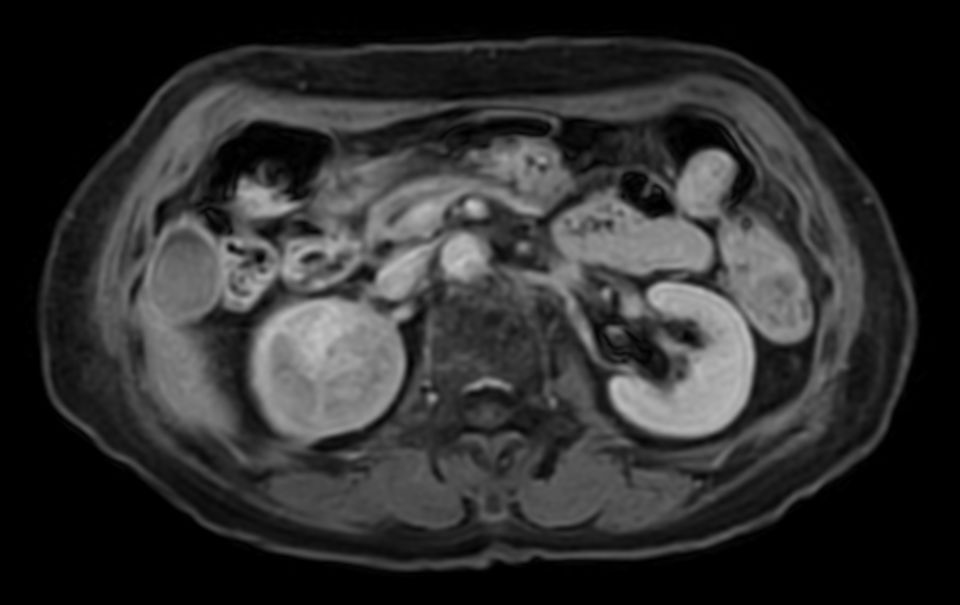

Patient with renal failure. ExamCard includes MultiVane XD to acquire motion-free diagnostic images and 4D FreeBreathing to perform multi-phase contrast-enhanced MRI studies.

Diffusion b800 - Free Breathing

Diffusion b800 (ADC) - Free Breathing